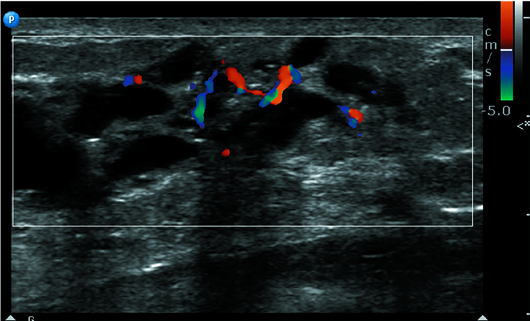

Targeted lateral breast ultrasound demonstrated significant ductal ectasia of variable caliber with associated ductal calcifications and vascularity on Doppler (Figures 3 and 4).

Figure 3

Figure 4